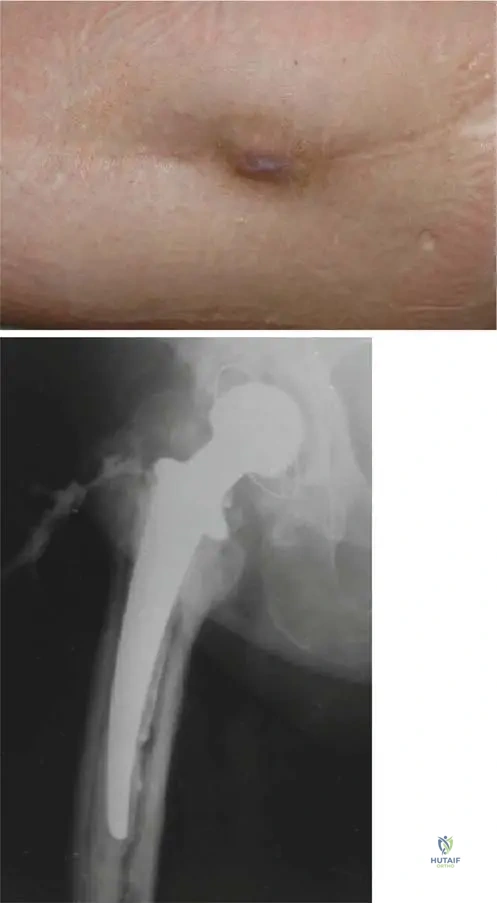

A 60-year-old patient presents with chronic hip pain. Radiographs show significant lytic destruction in the proximal femur with concentric narrowing of the femoral neck, as depicted in the image. This finding is characteristic of which aspect of Gorham's disease?

View Answer & Explanation

Correct Answer: C

Rationale: The image (Fig. 8.57) shows "Lytic destruction in the proximal femur with concentric narrowing of the femoral neck," which is a direct visual representation of the "massive, progressive osteolytic changes" that define Gorham's disease. Main Distractor: Option B, malignant bone tumor infiltration, is incorrect. While it can cause lytic lesions, Gorham's disease is a benign vascular process, and the pathology explicitly states no cytological atypia, ruling out malignancy.

A 45-year-old male presents with a "vanishing bone" phenomenon in his left leg. An AP radiograph of the left femur, as shown, demonstrates complete resorption of the diaphysis. This radiographic appearance is a hallmark of Gorham's disease and signifies what?

Correct Answer: B

Rationale: The image (Fig. 8.62) shows "complete resorption of diaphysis," which is an extreme manifestation of the "massive, progressive osteolytic changes" characteristic of Gorham's disease. This represents extensive and advanced destruction. Main Distractor: Option D, early stages of bone healing, is incorrect. The image clearly shows severe bone loss, which is the opposite of early healing. While sclerotic bone may accompany healing later, complete resorption is a destructive phase.